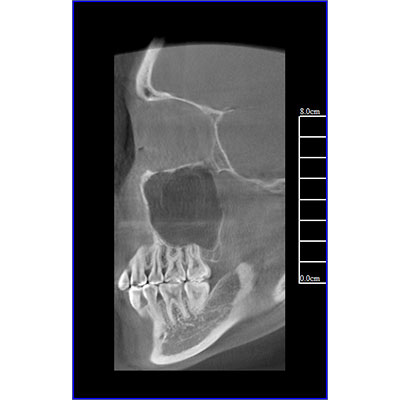

該款牙科CBCT產(chǎn)品采用動態(tài)平板探測器,獲得三維圖像的同時還具有數(shù)字化全景功能,廣泛應用于口腔頜面外科、正畸科、正頜外科、種植科、牙體科、顳下頜關節(jié)科等術前術后。

專有三維重建算法,可提供任意位置高清斷層影像。

可同時觀察軸向面、冠狀面和矢狀面圖像,方便臨床診斷。